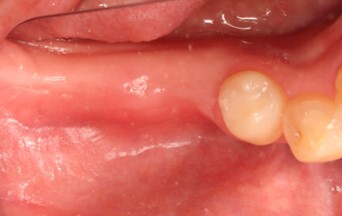

遊離歯肉移植

インプラント手術後少し治癒を待ってから、今度は遊離歯肉移植術を行いました。

術後2か月の写真。歯肉からインプラントの頭部分が見えています。

その周囲には薄いピンク色をした歯肉が囲んでいます。

ここまで歯肉に囲まれていると清掃性が向上します。